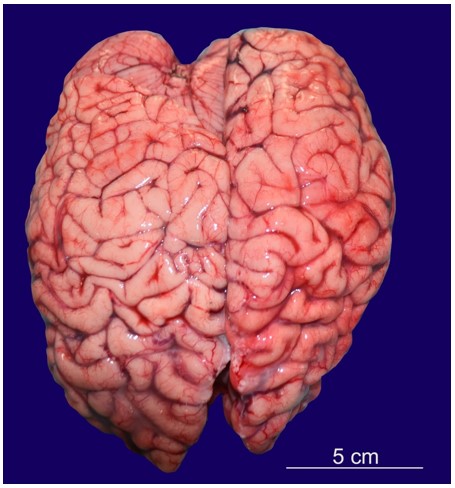

On autopsy, muscle wasting was noted in both upper and lower limbs. Clubbing of nails was present. There was scoliosis of the spine with the convexity of the thoracic spine towards the right side and convexity of the lumbar spine towards the left side. The cranial cavity was asymmetrical, with the left side larger than the right side. The floor of the anterior cranial fossa was more arched. In the posterior cranial fossa, the left side was larger, deeper, and more spacious. In contrast, the right side was smaller and compressed. The brain weighed 632 g (Normal average weight of the brain at 13 years of age is 1243 g)4 and was grossly asymmetrical. The left occipital lobe was larger, whereas the right occipital lobe was smaller and compressed (Figure 1).

The right frontal lobe was larger than the left frontal lobe.